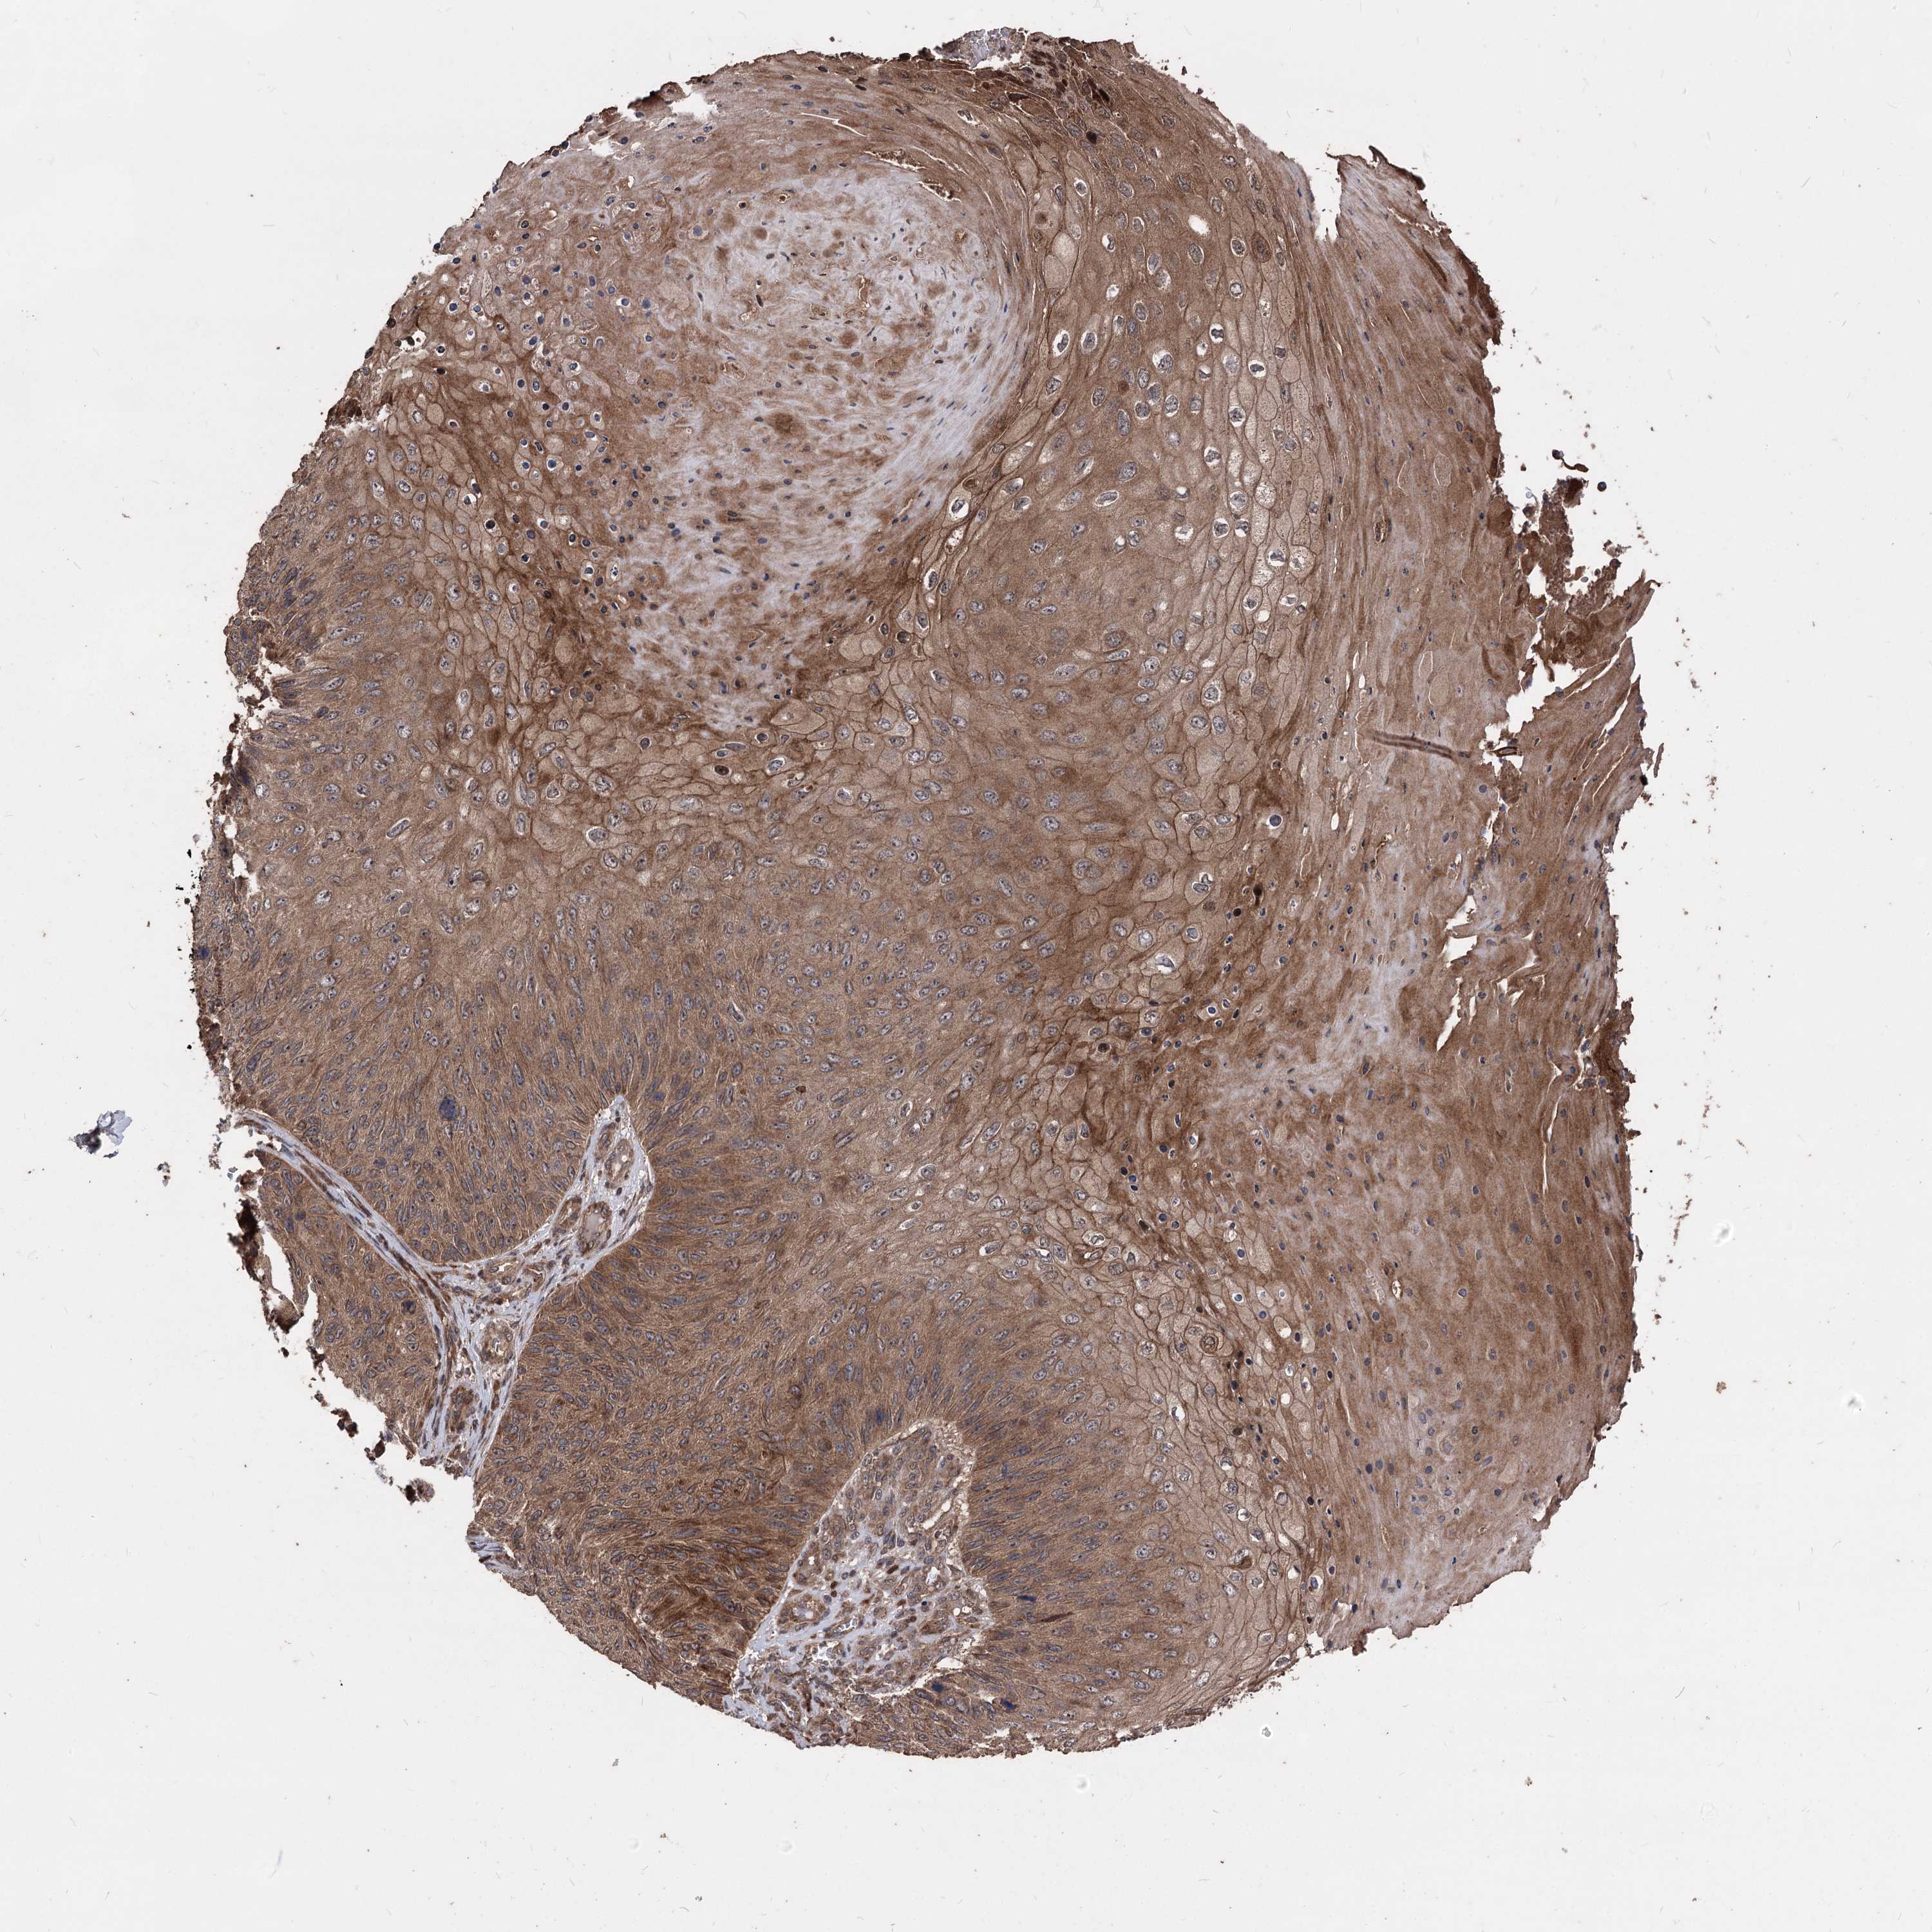

SKIN CANCER - Protein expressioni

A mouse-over function shows sample information and annotation data. Click on an image to view it in a full screen mode. Samples can be filtered based on level of antibody staining by selecting one or several of the following categories: high, medium, low and not detected. The assay and annotation is described here.

Antibody staining in the annotated cell types in the current human tissue is reported as not detected, low, medium, or high, based on conventional immunohistochemistry profiling in selected tissues. This score is based on the combination of the staining intensity and fraction of stained cells.

Each image is clickable and will lead to virtual microscopy that enables deeper exploration of all samples and also displays staining intensity scores, fraction scores and subcellular localization as well as patient and tissue information for each sample.

Squamous cell carcinoma, metastatic, NOS